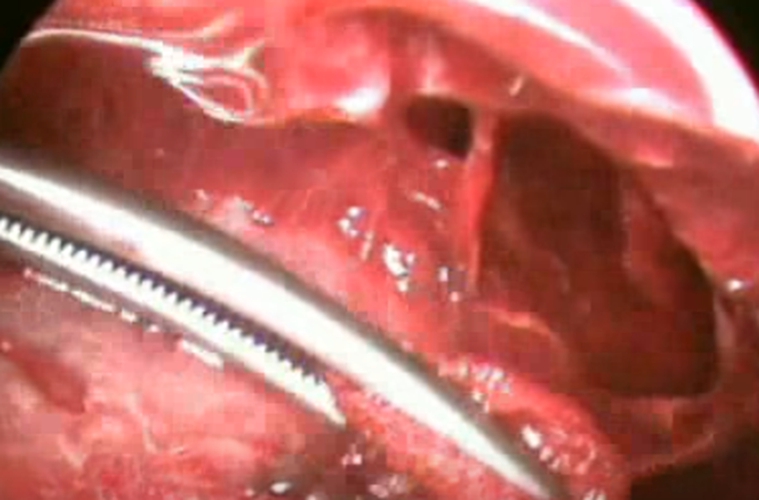

結核性胸膜炎胸腔鏡

結核性胸膜炎引流

結核性胸膜炎胸腔鏡的